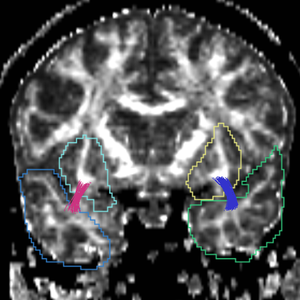

Region

caseD00917

caseD00920

caseD00924

caseD00928

caseD00935

caseD00936

caseD00938

caseD00939

caseD00940

Uncinate Fasciculus

Internal Capsule

Fornix

Cingulum

Arcuate Fasciculus